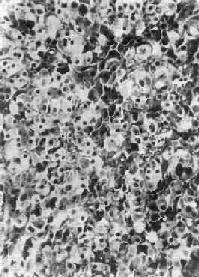

图15-16 肾上腺皮质腺瘤

肾上腺皮质腺瘤与局灶性结节性增生的病变相似,两者可以并发。腺瘤通常是单侧单发性,并有薄层包膜,对周围组织有压迫现象,为鉴别的主要点。大小直径为1~5cm,切面黄色,有时呈红褐色,镜下多为类似束状带的泡沫状透明细胞,含有丰富类脂质,有时由类脂含量少的嗜酸性细胞构成,或者两种细胞混合存在。瘤细胞排列成团,由含有毛细血管的少量间质分隔(图15-16)。部分腺瘤为功能性,可引起醛固酮增多症或Cushing综合征,在形态上与非功能性腺瘤没有区别。